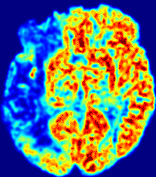

LesionRefer to captionRefer to captionRefer to captionRefer to captionRefer to captionRefer to caption𝐕rgbsubscript𝐕𝑟𝑔𝑏{\bf{V}}_{rgb}Refer to captionRefer to captionRefer to captionRefer to captionRefer to captionRefer to caption𝐕2subscriptnorm𝐕2{\|\bf{V}}\|_{2}Refer to captionRefer to captionRefer to captionRefer to captionRefer to captionRefer to captionRefer to caption3.53.53.52.82.82.82.12.12.11.41.41.40.70.70.70.00.00.0(mm/s)𝑚𝑚𝑠(mm/s)D𝐷DRefer to captionRefer to captionRefer to captionRefer to captionRefer to captionRefer to captionRefer to caption0.0200.0200.0200.0160.0160.0160.0120.0120.0120.0080.0080.0080.0040.0040.0040.0000.0000.000(mm2/s)𝑚superscript𝑚2𝑠(mm^{2}/s)Slice #1Slice #2Slice #3Slice #4Slice #5Slice #6

Figure 3: PIANO feature maps for one stroke patient, where the lesion is located in the left hemisphere. Top row: segmented stroke lesion region (white) on different slices, obtained from ISLES 2017. The corresponding slices for the PIANO feature maps are shown in the following rows.

For a better insight into an estimated velocity field 𝐕𝐕{\bf{V}} and diffusion field 𝐃𝐃{\bf{D}}, we compute the following maps: (1) 𝐕rgbsubscript𝐕𝑟𝑔𝑏{\bf{V}}_{rgb}: Color-coded orientation map of 𝐕=(Vx,Vy,Vz)T𝐕superscriptsuperscript𝑉𝑥superscript𝑉𝑦superscript𝑉𝑧𝑇{\bf{V}}=(V^{x},V^{y},V^{z})^{T}, obtained by normalizing 𝐕𝐕{\bf{V}} to unit length and mapping its 3 components to red, green, blue respectively; (2) 𝐕2subscriptnorm𝐕2\|{\bf{V}}\|_{2}: 222 norm of 𝐕𝐕{\bf{V}}; (3) D𝐷D: scalar field in Eq. 5.

Fig. 3 and Fig. 4 show the PIANO feature maps estimated from two ISLES 2017 patients: all are highly consistent with the lesion in both cases. Details of the blood flow trajectories are revealed in 𝐕rgbsubscript𝐕𝑟𝑔𝑏{\bf{V}}_{rgb} by the ridged patterns and the sharp changes of colors in the unaffected (right) hemisphere, while the flat patterns appearing within the lesion provide little directional information about the velocity and indicate low velocity magnitudes. Velocity magnitudes are more directly visualized via 𝐕2subscriptnorm𝐕2\|{\bf{V}}\|_{2}, from which one can easily locate the lesion where 𝐕2subscriptnorm𝐕2\|{\bf{V}}\|_{2} is low. D𝐷D also indicates lower diffusion values in the lesion, though with less contrast potentially due to the fact that it captures the accumulated effect of CA diffusion at the voxel-level.